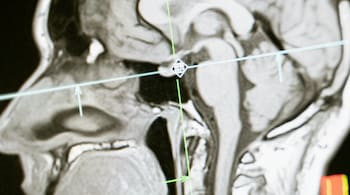

Studies reveal that small amounts of radiation can leave a mark on the body. How much harm occurs depends on the strength of the radiation, how long someone is exposed, and the way it’s administered. Effects can appear immediately, or build gradually.

In the short term, people may feel nauseous, weak, or dizzy. Skin can get irritated, even burned, and hair might fall out in areas exposed. “Radiation doesn’t just hit the body, it can affect the nervous system too,” medical experts warn.

Long-term impacts can be far more serious. Studies link exposure to a higher risk of cancers such as leukemia, thyroid, and breast cancer. Organs like the liver, kidneys, and bone marrow may suffer damage. Fertility issues, cataracts, and a weaker immune system are also possible, along with genetic effects that could affect future generations.